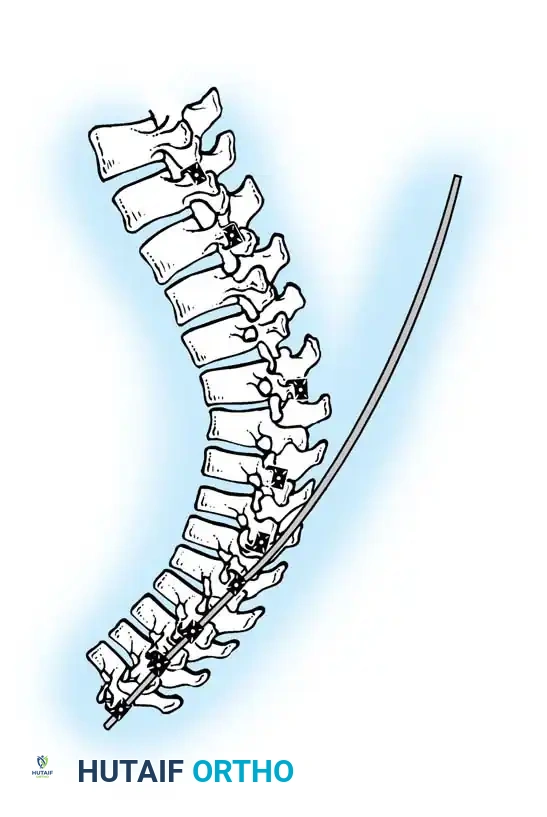

4. Rod Contouring and Reduction

Two rigid rods (typically 5.5mm or 6.0mm Cobalt Chrome or Titanium) are meticulously contoured. The rods must be under-contoured relative to the patient's current deformity but over-contoured relative to the desired final physiological kyphosis (aiming for 40 degrees).

Insertion of the contoured rod into the pedicle screw construct.

The reduction is achieved via a cantilever maneuver. The rods are seated in the distal foundation screws first. Using reduction tubes and set screws, the rod is sequentially drawn into the apical and proximal screws. This maneuver translates the spine to the rod, simultaneously correcting the kyphosis and restoring sagittal balance.